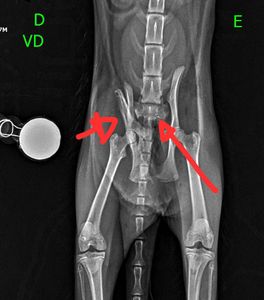

Ela sofreu múltiplas fraturas na pelve e na coluna, além de lacerações nas patas. O quadro é muito sério e ela corre risco de ficar paraplégica.